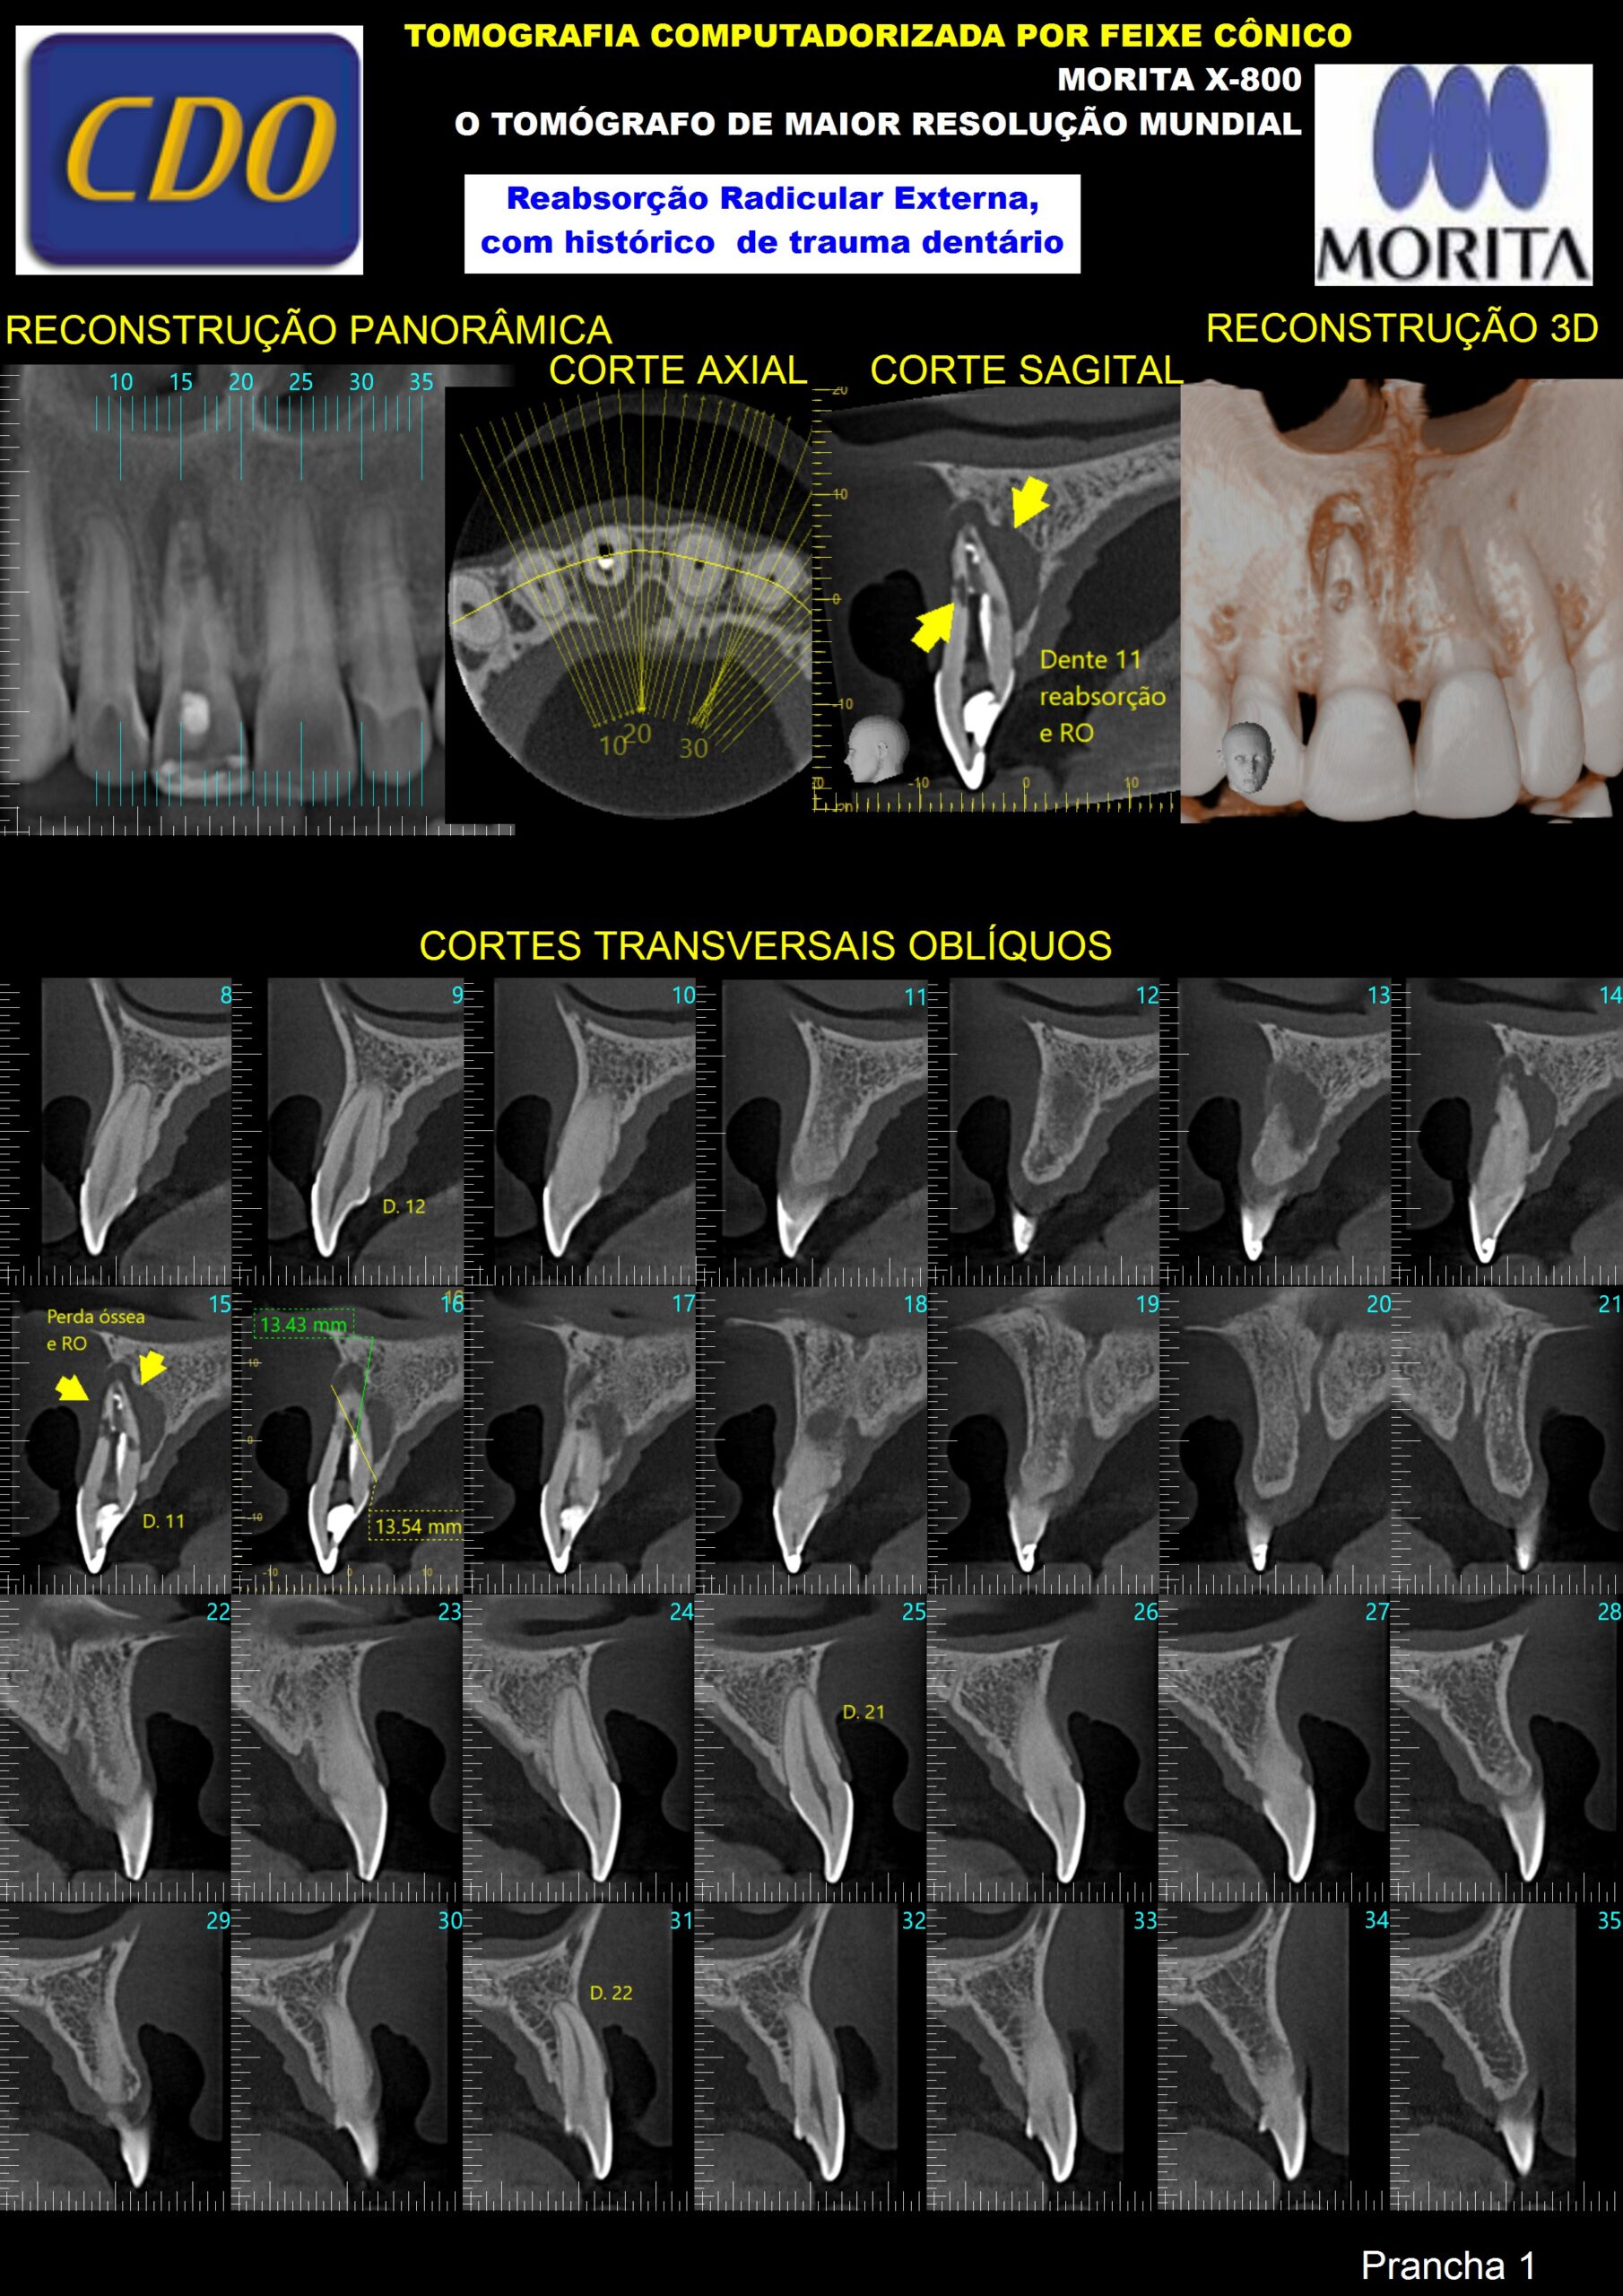

blog.digitalvolp.com.brTOMOGRAFIA COMPUTADORIZADA DE ALTA RESOLUÇÃO – CDO Radiografias

blog.digitalvolp.com.brTOMOGRAFIA COMPUTADORIZADA DE ALTA RESOLUÇÃO – CDO Radiografias